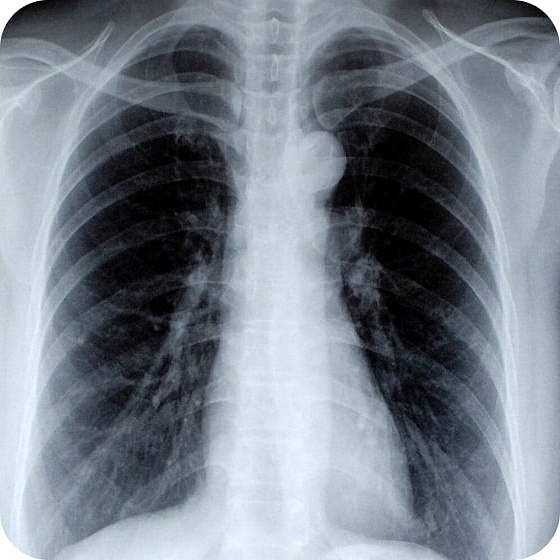

Рентген

Быстрое получение изображения делает рентген незаменимым при острых травмах, кровотечениях или подозрениях на переломы и вывихи

- Рентгеновские снимки делаются быстро, обычно в течение нескольких минут, что особенно важно в острых ситуациях.

- Обеспечение высокой детализации костных структур: идеален для выявления переломов, вывихов, аномалий костей и суставов.

- Позволяет выявить пневмонию, туберкулез, сердечную гипертензию и другие патологические состояния органов грудной клетки.

- Рентген помогает отличить одни заболевания от других, например, различать опухоли, кисты, воспалительные процессы или кальцинаты.